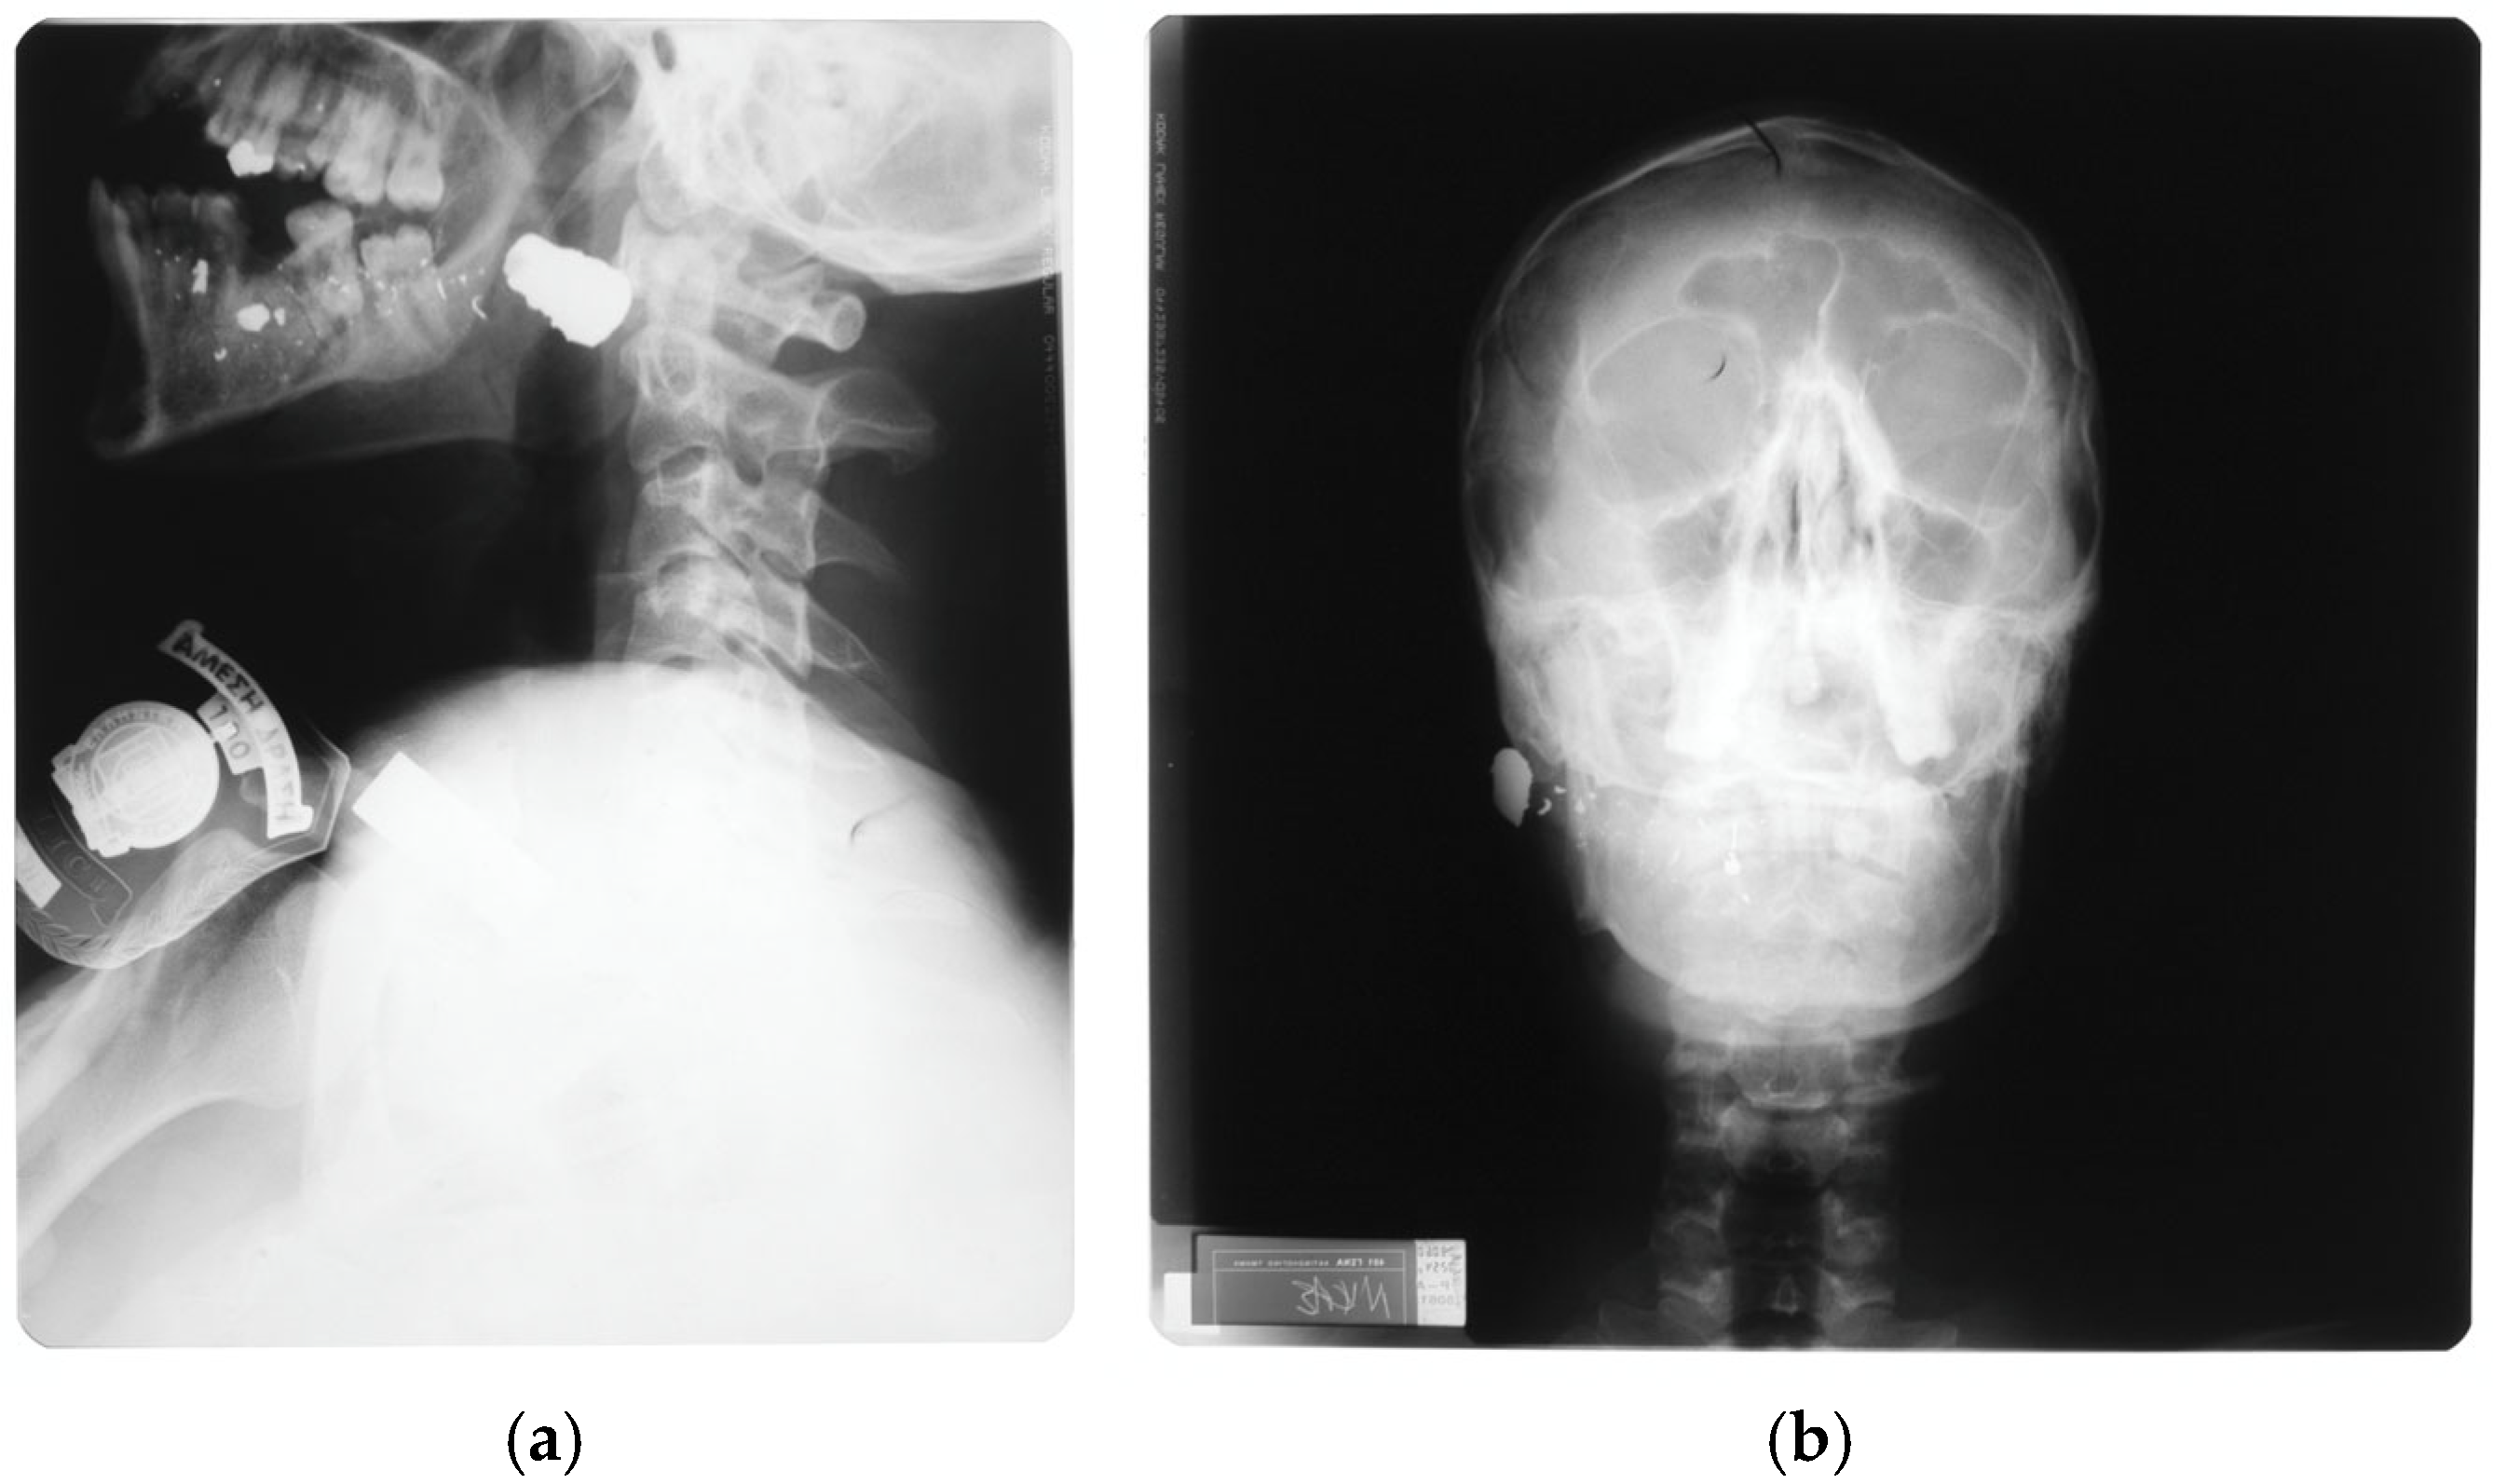

- Oehmichen, M.; Meissner, C.; König, H.G.; Gehl, H.B. Gunshot injuries to the head and brain caused by low-velocity handguns and rifles: A review. Forensic Sci. Int. 2004, 146, 111–120. [Google Scholar] [CrossRef]

- Cooper, P.R. Gunshot wounds to the brain. In Head Injury, 3rd ed.; Cooper, P.R., Ed.; Williams & Wilkins: Baltimore, MD, USA, 1993; pp. 355–371. ISBN 0-683-02108-7. [Google Scholar]

- Aarabi, B.; Eisenberg, H. Surgical management and prognosis of penetrating brain injury. In Youmans & Winn Neurological Surgery, 8th ed.; Winn, H.R., Ed.; Elsevier: Philadelphia, PA, USA, 2023; pp. 3092–3104. ISBN 978-0-323-66192-8. [Google Scholar]

- Majors, J.S.; Brennan, J.; Holt, G.R. Management of high-velocity injuries of the head and neck. Facial Plast. Surg. Clin. North. Am. 2017, 25, 493–502. [Google Scholar] [CrossRef]

- Kirkpatrick, J.B.; Di Maio, V. Civilian gunshot wounds of the brain. J. Neurosurg. 1978, 49, 185–198. [Google Scholar] [CrossRef] [PubMed]